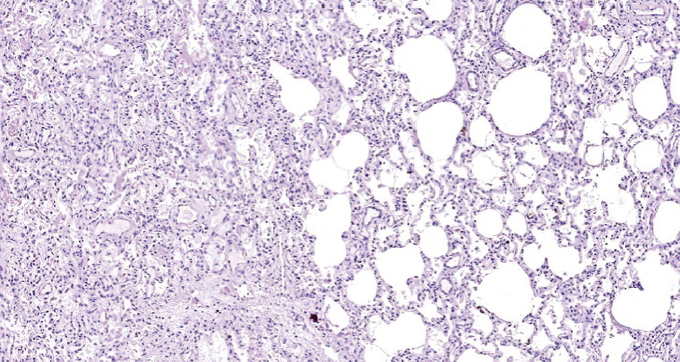

При патологоанатомическом исследовании — ткань легких с диффузными ателектазами, чередующимися с небольшими эмфизематозно расширенными участками, мелкоочаговыми кровоизлияниями в расширенные межальвеолярные перегородки (рис. 1). Большая часть альвеол звездчатой формы, очагово заполнены серозно-фибринозным экссудатом (рис. 2), слущенными альвеолоцитами, альвеолярными макрофагами (рис. 3). Часть альвеол выстлана гиалиновыми мембранами (рис. 4). Сосуды микроциркуляторного русла, расположенные в межальвеолярных перегородках, округлой формы, в просвете большей части которых определяются нити фибрина. Эндотелиальные клетки, выстилающие сосуды, набухшие, овальной формы, другие — более вытянутые, сохраненные не на всем протяжении стенки сосуда. Бронхи среднего и более крупного калибра звездчатой формы, стенка преимущественно утолщена за счет отека и склероза подслизистого слоя. Слизистая оболочка бронхов представлена цилиндрическим эпителием с дистрофическими изменениями, местами слущенным, в сохраненных участках с явлением пролиферации. В просвете бронхиол и более крупных бронхов выявляются десквамированный эпителий, единичные эритроциты, макрофаги. Кроме этого, преимущественно перибронхиально — диффузная лимфоцитарная инфильтрация с примесью умеренного количества нейтрофильных лейкоцитов; разрастание соединительной ткани, образование мелких единичных лимфоидных фолликулов.

Рис. 1. Чередование ателектазов с эмфизематозно измененными участками легкого. Окраска гематоксилином и эозином. Ув. ×100 / Fig. 1. Alternation of atelectasis with emphysematous altered areas of the lung. Stained with hematoxylin and eosin. Magnification ×100